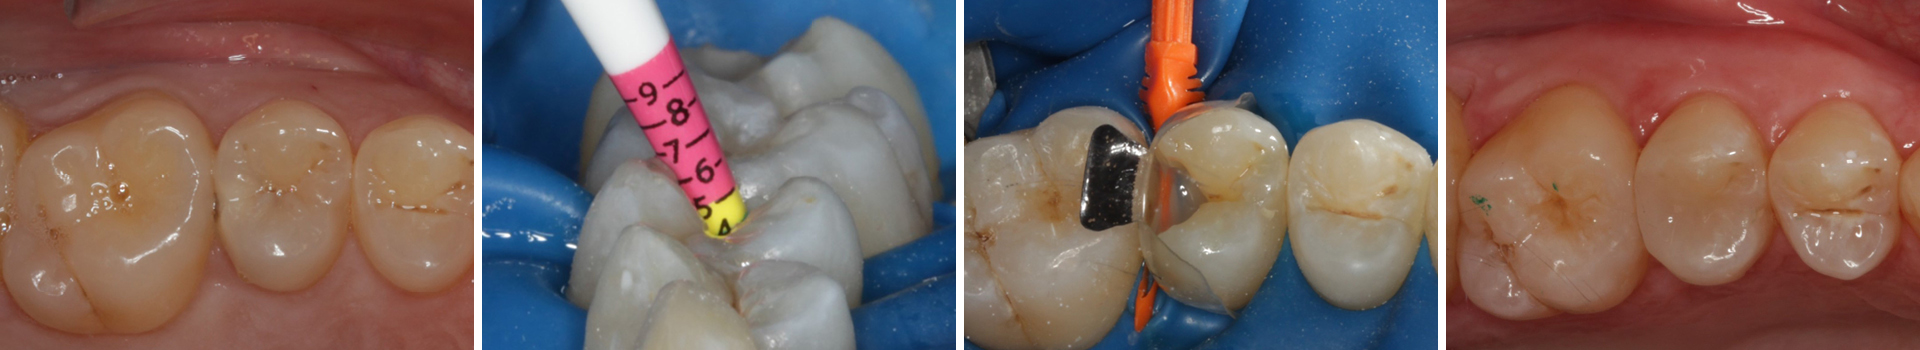

Abbildung 2

Bissflügelröntgenaufnahme

Abbildung 3

Quadrantenisolierung mit Kofferdam (x-heavy)

Abbildung 4

Schutz des Nachbarzahnes und des Kofferdams mit wiederverwandter Bioclear Biofit Matrize (gereinigt und sterilisiert); Separation zur Applikation der Matrize mit Heidemannspatel

Abbildung 5

Defektdarstellung

Abbildung 6

Kariesexcavation pulpennah mit Kunststoffrosenbohrer

Abbildung 7

Zustand nach Dentinversiegelung mit Einkomponentenadhäsiv und Lichthärtung

Abbildung 8

Nach Anschrägung der Schmelzränder und Reinigung der Kavitätenränder mit diamantierter Hubfeile

Abbildung 9

Height Indicator vor Auswahl der passenden Evolve Matrize

Abbildung 10

Nach Applikation der Matrize: Evolve Schwarz Prämolar- 7 mm; Schmelzätzung

Abbildung 11

Nach Spray und Trocknung der Kavität

Abbildung 12

Nach erneuter Applikation des Einkomponentenadhäsivs und tief approximal eines fließfähigen Bulkkomposits, der Lichthärtung, und der Applikation des Bioclear Diamond Wedges Medium

Abbildung 13

Weiteres Flowkomposit appliziert und Bioclear Twin Ring Universal angebracht

Abbildung 14

Kavität gefüllt (Injektion Moulding: Flowkomposit, erwärmtes Seitenzahnkomposit aus Karpule)

Abbildung 15

Matrize, Twinring, und Keil entfernt; weitere Lichthärtung von bukkal und oral

Abbildung 16

Überschussentfernung/ „Anpolieren“ u.a. trocken mit Sandpapierscheibe

Abbildung 17

Zahnseidenkontrolle: kein Überschuss, satter Kontaktpunkt

Abbildung 18

Fertige Restauration